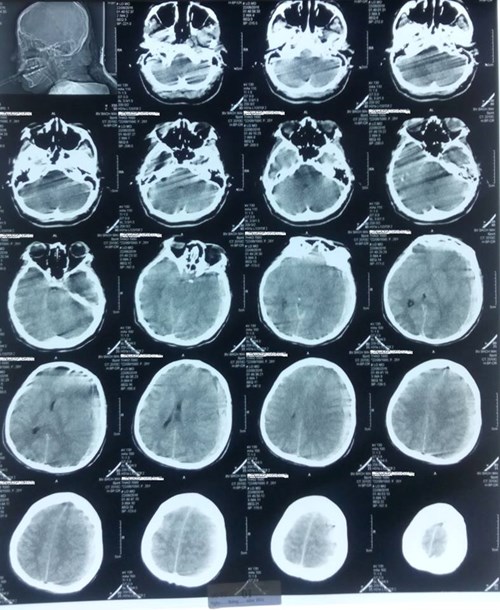

Ngay lập tức bệnh nhân được đặt ống nội khí quản, thở máy, và chụp

cắt lớp vi tính sọ não.

Hình ảnh chụp cắt lớp vi tính sọ não sản phụ.

Kết quả chụp cho thấy sản phụ bị tụ máu dưới màng

cứng bán cầu não trái gây hiệu ứng khối mạnh. Phù não lan tỏa dẫn

tới hôn mê. Bệnh nhân có nguy cơ tử vong rất cao nếu không được phẫu thuật lấy

máu tụ và mở sọ giảm áp sớm.